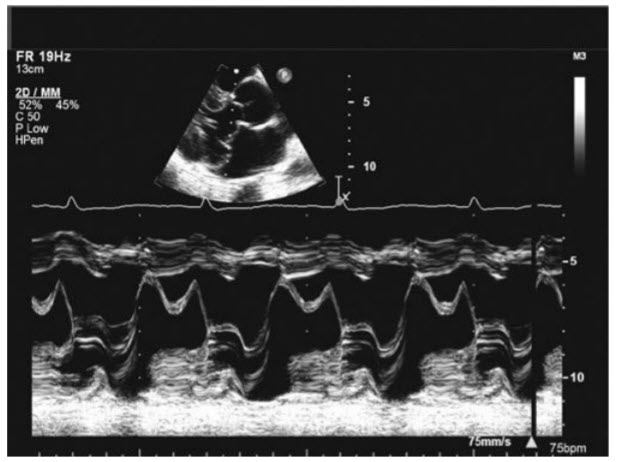

This M-mode tracing (Fig. below)

demonstrates a patient with

Mitral Valve Prolapse (MVP). The M-mode trace is performed through the MV in a patient with myxomatous MV disease with bileaflet prolapse. Note the marked dip backward of the MV leaflets after the closure point (see Fig. in question). Note that there is full systolic range of motion creating the “M” trace of the anterior mitral leaflet and the normal “W” trace of the posterior leaflet. This is in contrast with a normal MV M-mode, which would not have the systolic dip (Fig. below A). Thus, there is no rheumatic MS, which would look like Figure below B in which there are still pliable but tethered leaflets causing a loss of the normal “M” and “W” appearance of the mitral leaflets. More advanced MS with thickened and calcified leaflets would have thicker and brighter appearance of the leaflets together with more restriction of the leaflet motion (Fig. below C). M-mode for a patient with HOCM and SAM would appear like the images in Figure below D and E. Note the SAM of the mitral leaflets in Figure below D and the early closure of the AV in Figure below E (compared with the M-mode of a normal AV [Fig. below F]).